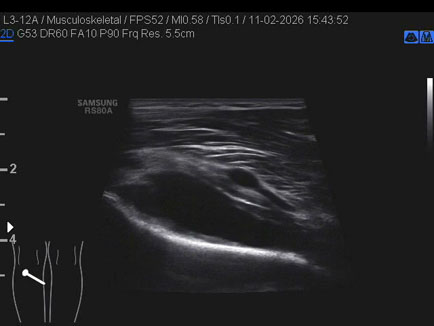

Data inserimento: 13/02/2026

Ecografia del: 11/02/2026

Strumento: Samsung

Sonda: Lineare

Commento all'esame: rottura giunzionale muscolo-tendinea del popliteo.

Conclusioni: rottura miotendinea del muscolo popliteo sinistro (myotendinous tear of the left popliteus muscle).

Realizzazione: Dr. F. Pietro Tarini - Gubbio (PG)